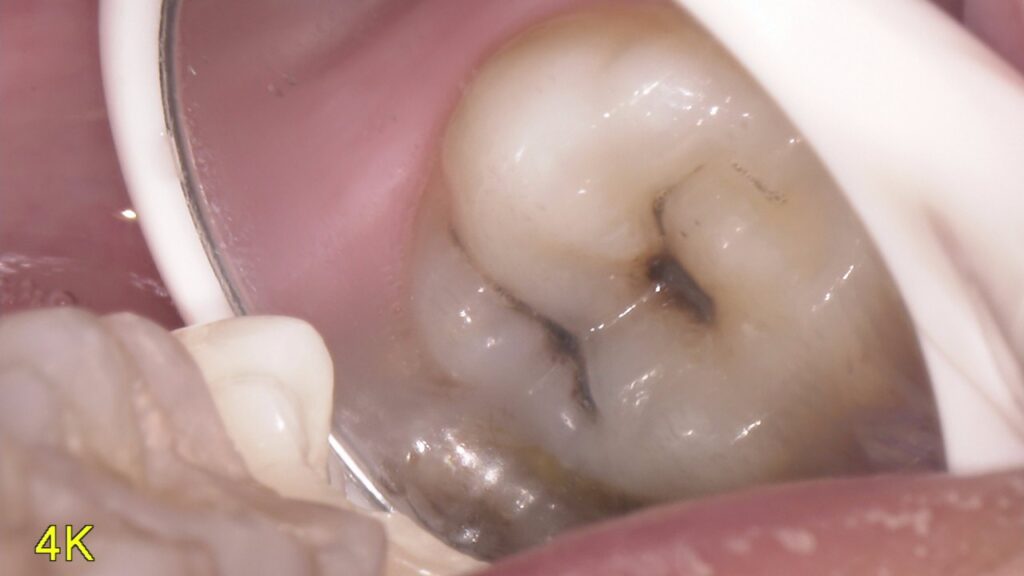

虫歯って患者さん本人には見えない位置にあったりしてなかなわかりにくいですよね

そのために当院では口腔内カメラを内蔵したマイクロスコープを使用して口腔内を説明しています。

写真を撮ったり、動画を撮ったりいろいろ使えるので重宝しています。

今回の写真は普段見えない位置の虫歯を撮影してみました。まだ小さいので症状はなにもないですが放置していたら広がってかけたり痛みが出てくると考えられるのでその前にしっかりと治していくのが大事です。

どんだけお話しするより現物を見てもらったほうがイメージわきますしどうなってるかわかるのでやはり動画や写真は大事なんだなと痛感しています。